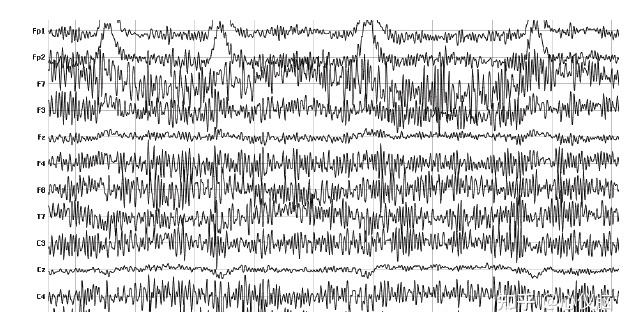

2.肌电伪迹

肌电由于肌肉收缩而产生。由于肌电不容易传导很远,颈部以下肌肉通常并不重要。头颈部肌肉运动时(例如皱眉,咬牙,吞咽,颈部肌肉紧张)是产生脑电伪迹的主要原因之一,波幅高,频率快,常表现为连续性的各种频率的尖头脉冲。